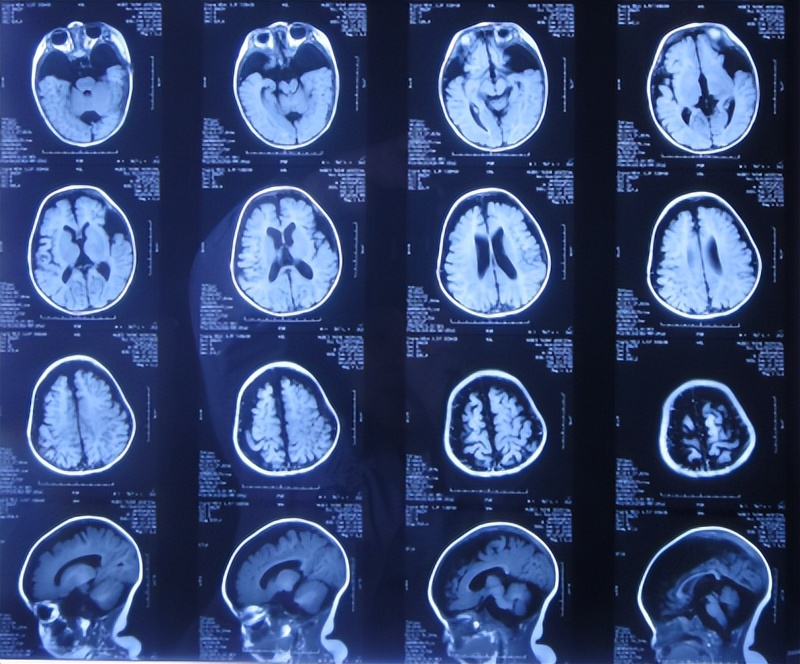

为治疗蛛网膜囊肿、脑积水,于2018年9月13日(发现蛛网膜囊肿后2天),家属带患儿住入第2家医院,湖北省十堰市某三甲医院,查头颅核磁示双颞叶蛛网膜囊肿、脑积水( 图-2 )。

图-2: 2018年9月13日头颅核磁